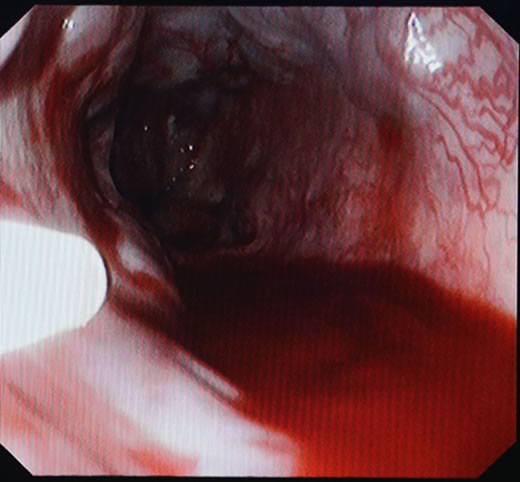

郎溪县人民医院成功开展了胃镜下食管静脉曲张硬化术

郎溪县人民医院消化内科与南京中大医院协作,成功开展了胃镜下食管静脉曲张硬化术。该技术适用于肝硬化合并食管静脉曲张破裂出血及预防再出血患者,减少患者反复出血带来的痛苦,提高生存质量。